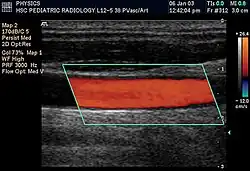

Doppler ultrasonography is medical ultrasonography that employs the Doppler effect to perform imaging of the movement of tissues and body fluids (usually blood),[1][2] and their relative velocity to the probe. By calculating the frequency shift of a particular sample volume, for example, flow in an artery or a jet of blood flow over a heart valve, its speed and direction can be determined and visualized.

Duplex ultrasonography sometimes refers to Doppler ultrasonography or spectral Doppler ultrasonography.[3] Doppler ultrasonography consists of two components: brightness mode (B-mode) showing anatomy of the organs, and Doppler mode (showing blood flow) superimposed on the B-mode. Meanwhile, spectral Doppler ultrasonography consists of three components: B-mode, Doppler mode, and spectral waveform displayed at the lower half of the image. Therefore, "duplex ultrasonography" is a misnomer for spectral Doppler ultrasonography, and more exact name should be "triplex ultrasonography".[3]

Colour Doppler shows the direction of the blood flow in red or blue (either towards or away from the transducer). Meanwhile, spectral Doppler not only shows the direction of blood flow, it also shows the phases (pulsatility) and acceleration of the blood flow. Any sudden changes in direction of blood flow produces audible sounds on the ultrasound machine.[3]

In spectral Doppler, the y-axis shows the direction and velocity of the flow. Meanwhile, the x-axis (as known as "baseline") shows the flow over time. The gradient at any point on the waveform would therefore shows the acceleration of the flow. In "antegrade" flow, the blood flows according to the normal flow within the circulatory system (e.g. veins flow towards the heart while arteries flows away from the heart). In "retrograde" flow, the flow would reverse (e.g. veins flow away from heart or arteries flow towards the heart). However, "retrograde" flow can be both abnormal or normal. For example, in portal hypertension, there is an abnormal portal venous flow where it flows away from the liver (hepatofugal flow) instead of the normal flow towards liver (hepatopetal flow). In jugular venous pressure waveform of the internal jugular vein, the retrograde "a" waveform is a normal flow due to right atrium contraction. Both antegrade or retrograde flow can be either towards or away from the probe transducer, depending on the position of the probe relative to the blood flow. Blood flow toward the transducer would appear above the baseline while blood flows away from the transducer will appear below the baseline. Waveform of the flow can be classified as: pulsatile (as in arteries), phasic (as in veins), non-phasic (as in diseased veins), and aphasic (no flow). Spectral broadening (thickness of the waveform) increases from large vessels (plug flow) to medium vessels (laminar flow) to small/stenotic/diseased vessels (turbulent flow) due to a larger variety of blood with different ranges of velocities in those with turbulent flow.[3]